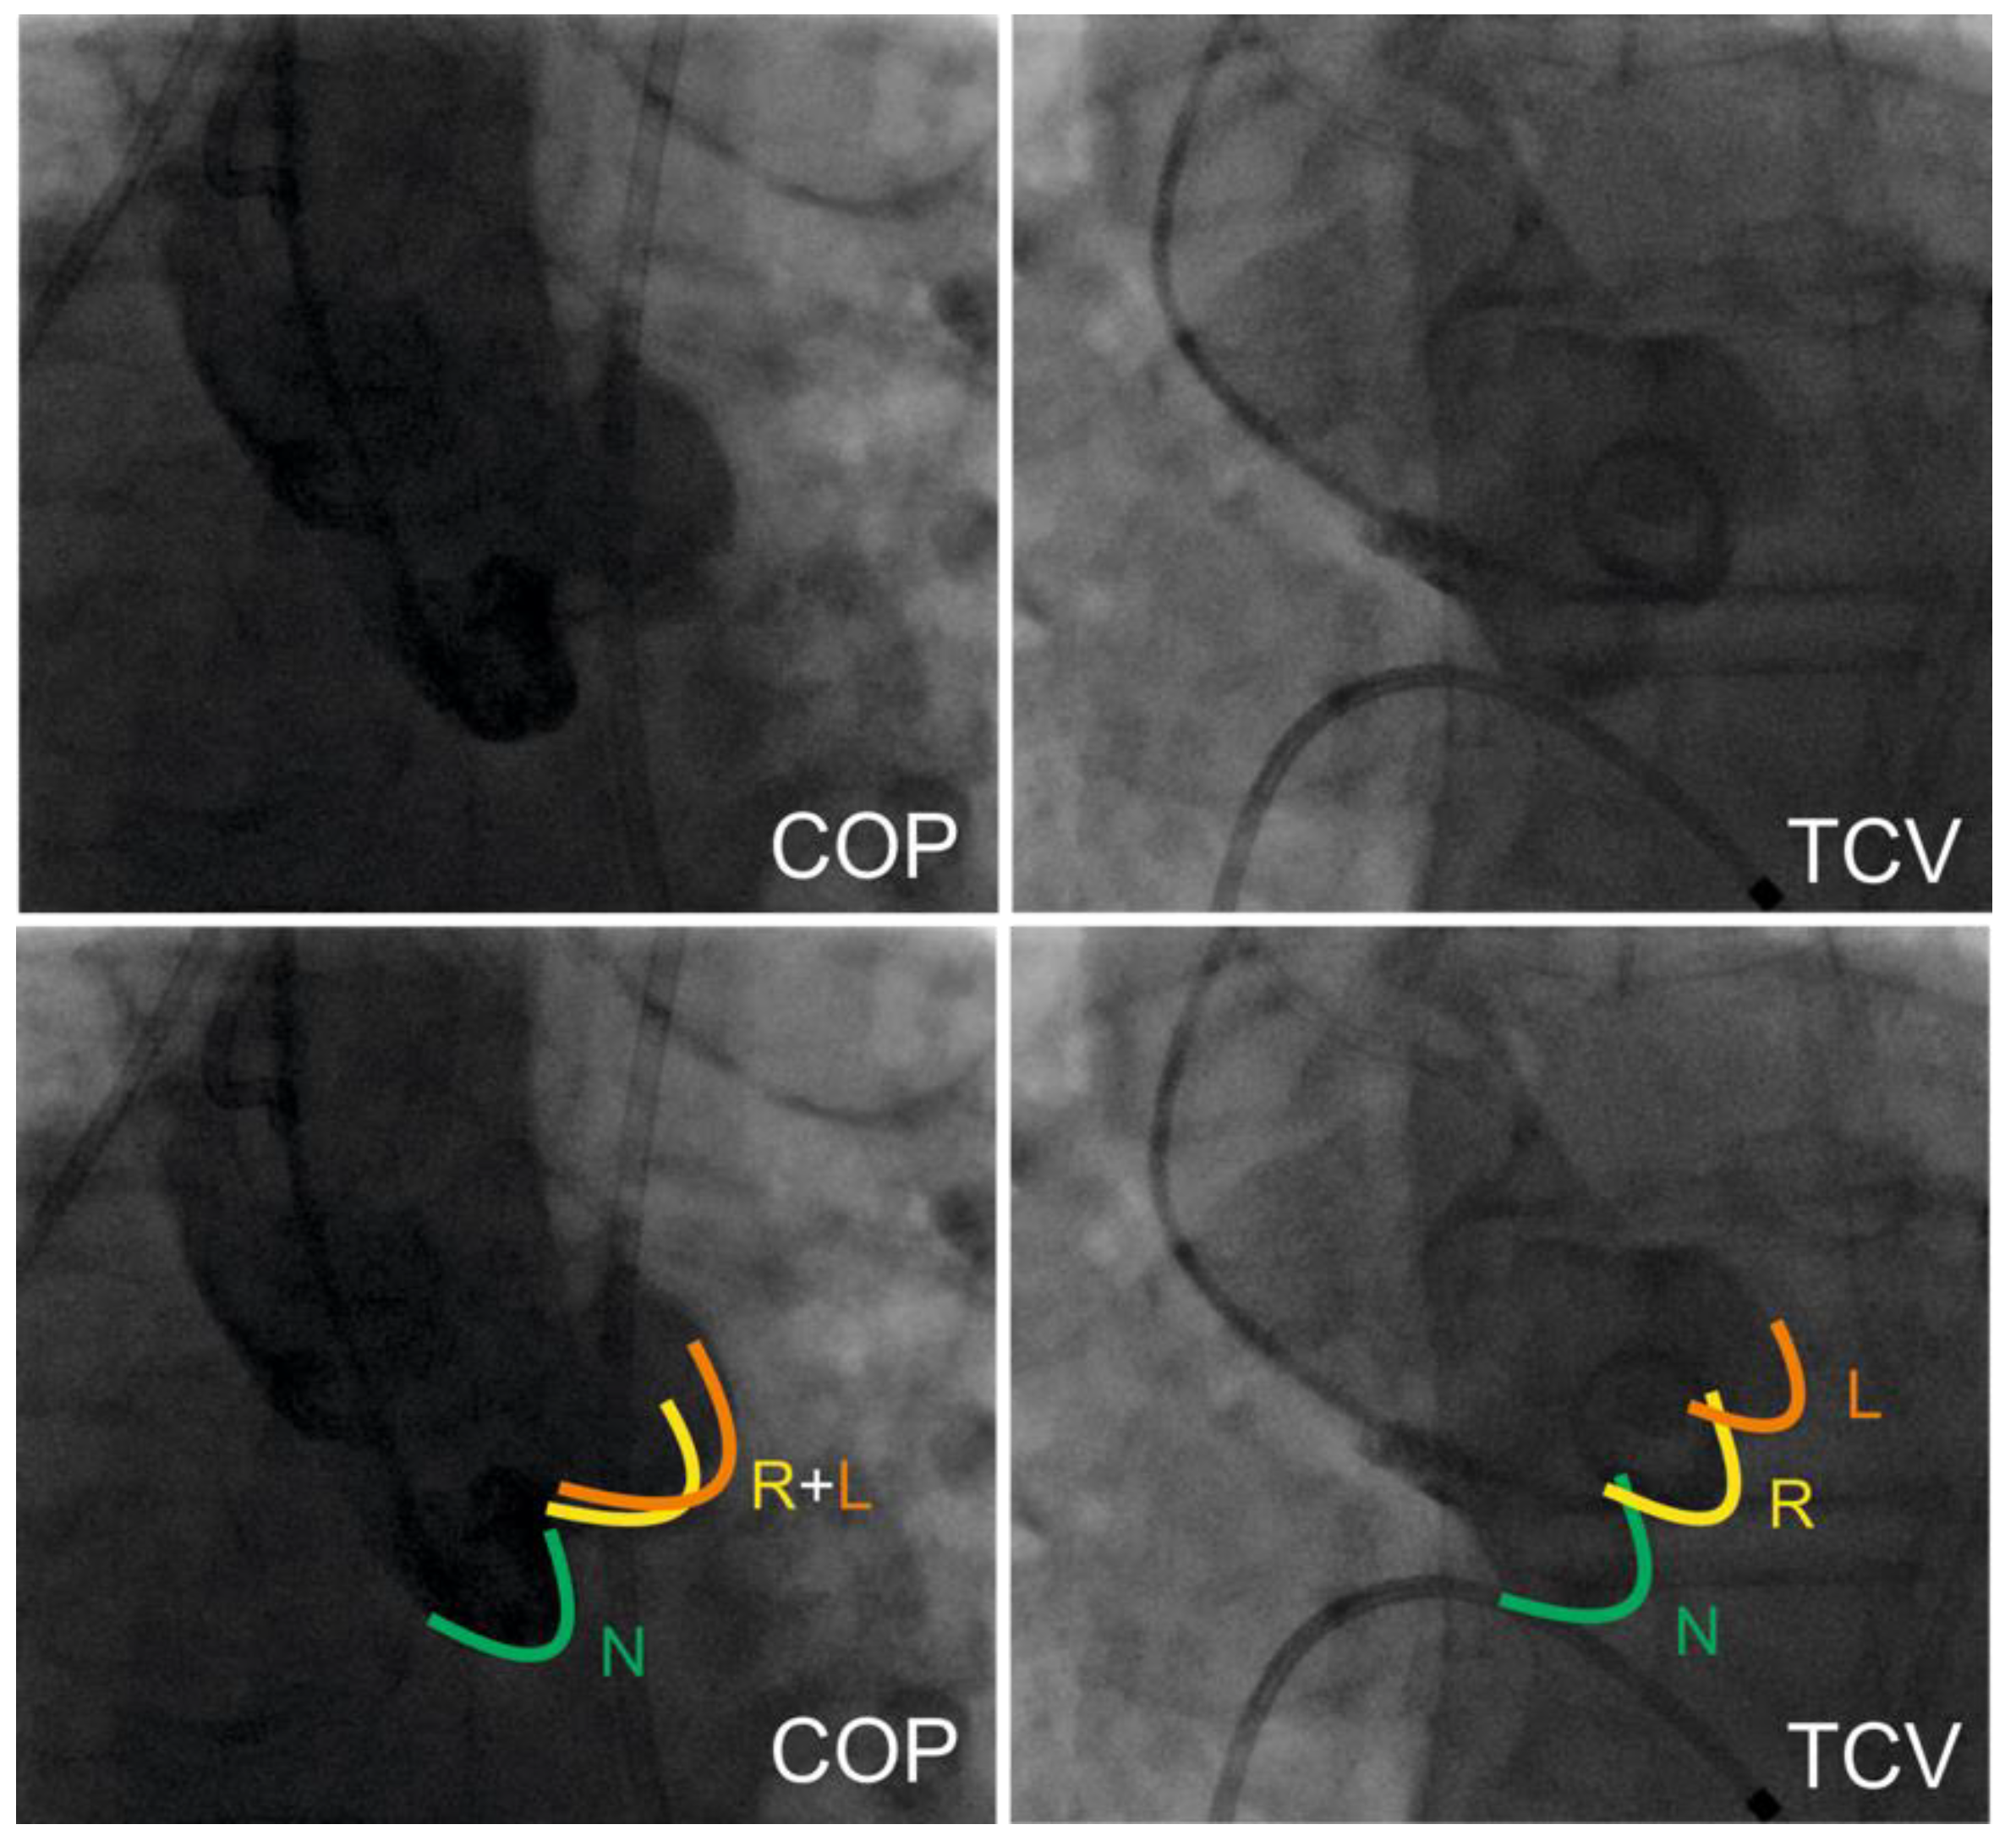

2.3. TAVR Procedure